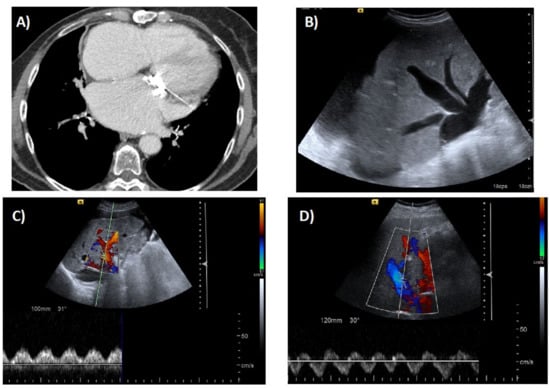

- Morales, A.; Hirsch, M.; Schneider, D.; González, D. Congestive hepatopathy: The role of the radiologist in the diagnosis. Diagn. Interv. Radiol. 2020. [Google Scholar] [CrossRef] [PubMed]

- Wells, M.L.; Venkatesh, S.K. Congestive hepatopathy. Abdom. Radiol. 2018, 43, 2037–2051. [Google Scholar] [CrossRef] [PubMed]